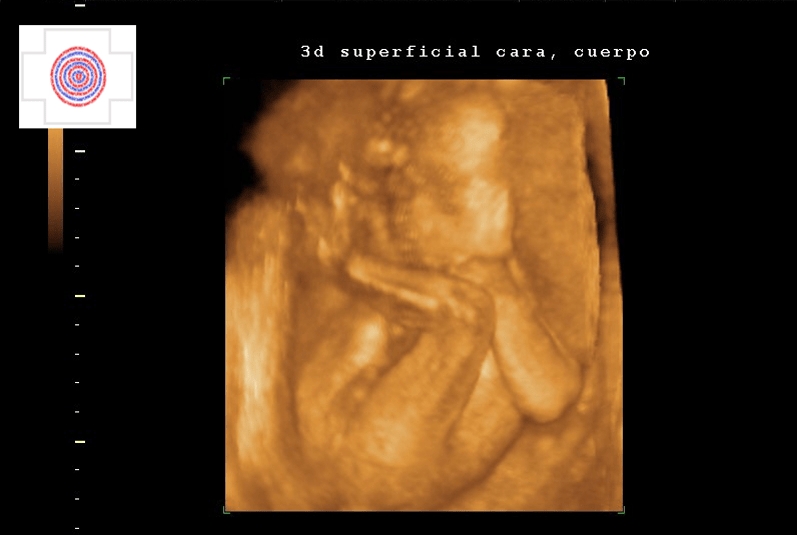

3D SUPERFICIAL, CARA, BOCA, NARIZ, PARPADOS